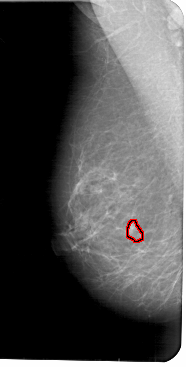

A_1776_1.LEFT_MLO

LEFT_MLO LINES 5491 PIXELS_PER_LINE 2776 BITS_PER_PIXEL 12 RESOLUTION 43.5 OVERLAY

FILE: A_1776_1.LEFT_MLO.OVERLAY

TOTAL_ABNORMALITIES 1

ABNORMALITY 1

LESION_TYPE MASS SHAPE IRREGULAR MARGINS ILL_DEFINED

ASSESSMENT 4

SUBTLETY 3

PATHOLOGY BENIGN

TOTAL_OUTLINES 1

BOUNDARY